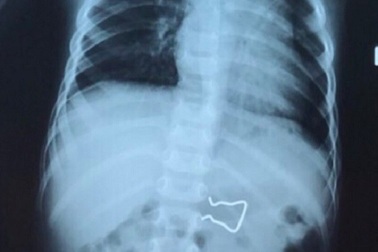

Móc sắt nằm gọn trong ruột bé 18 tháng tuổiHình ảnh X-quang phát hiện chiếc móc sắt sắc nhọn trong đường tiêu hóa của bệnh nhi, nguy cơ gây thủng ruột. Tai nạn nguy hiểm vừa xảy đến với cháu bé 18 tháng tuổi.